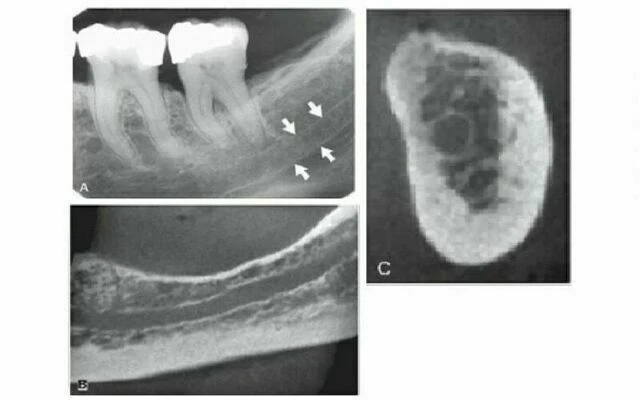

Ống dinh dưỡng

Ống dinh dưỡng chứa một bó thần kinh mạch máu và có hình ảnh dạng đường thấu quang với chiều rộng khá đồng đều. Chúng thường được thấy nhất ở phim quanh chóp ở hàm dưới chạy dọc từ phía dưới ống thần kinh xương ổ răng dưới đến một chóp răng hoặc vào khoảng giữa các răng cửa hàm dưới. Thấy được chúng trong khoảng 5% trường hợp trên tất cả bệnh nhân và thường ở người nam, da đen, người lớn tuổi và những người có huyết áp cao hoặc bệnh lý nha chu tiến triển. Chúng cũng cho thấy gờ xương mỏng, hữu ích khi đánh giá implant. Vì chúng có giải phẫu là khoảng trống bao quanh bởi thành là xương vỏ nên hình ảnh thường cho thấy biên giới xương dày. Đôi khi ống dinh dưỡng vuông góc với xương vỏ cho hình ảnh một vòng tròn thấu quang giống như hình ảnh thấu quang của bệnh lý. Gờ móng Gờ móng là một mào xương không đều nằm nên bề mặt trong của thân xương hàm dưới. Kéo dài từ vùng răng cối lớn thứ ba đến bờ dưới xương hàm dưới vùng cằm, nó đóng vai trò là chỗ bám của cơ hàm móng. Hình ảnh X quang chạy theo chiều nghiêng xuống và ra trước từ vùng răng cối lớn thứ ba đến vùng răng cối nhỏ, ở xấp xỉ mức chóp các răng sau.

Đôi khi hình ảnh chồng lên hình ảnh của các chân răng cối lớn. Bờ viền của hình ảnh gờ móng thường không rõ nhưng khá rộng với kích thước khác nhau. Tuy nhiên, cũng có thể thấy điều ngược lại, tại vị trí gờ tương đối đậm đặc và biên giới sắc nét.